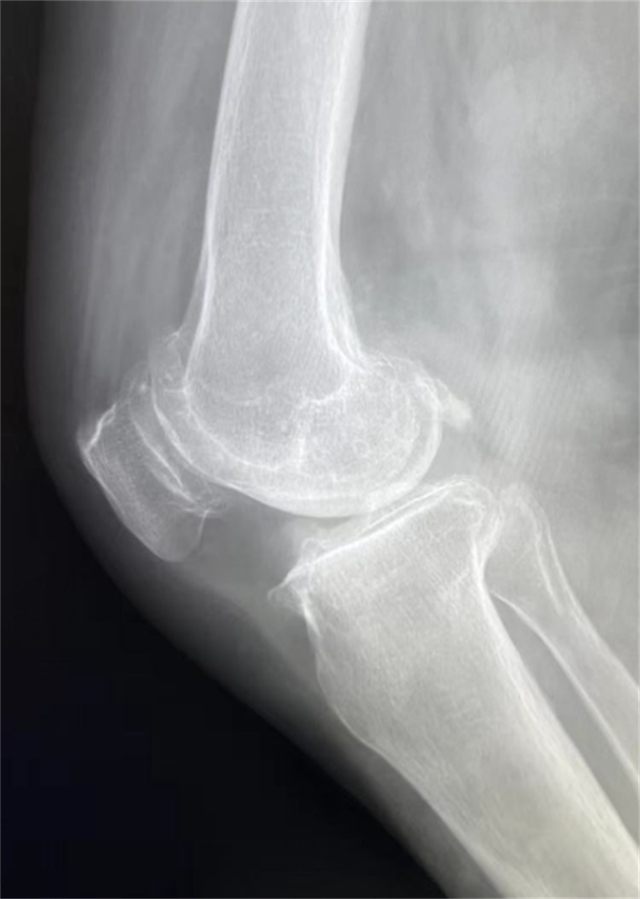

患者术前影像资料